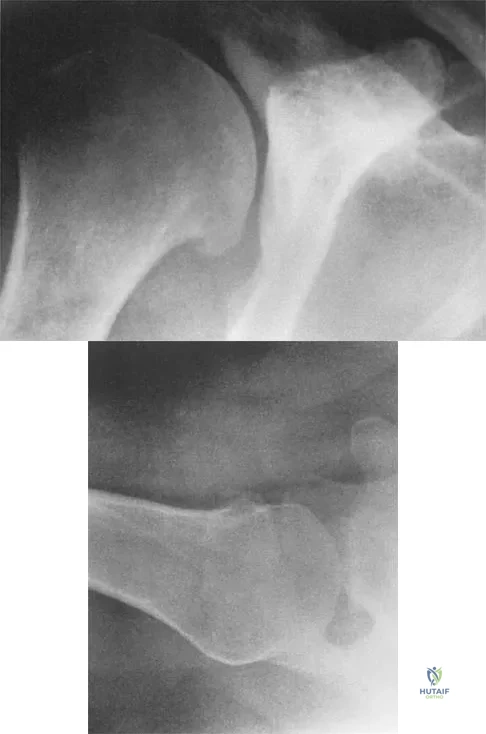

Figures 5a and 5b show the radiographs of a 45-year-old patient. What is the most likely diagnosis?

Explanation